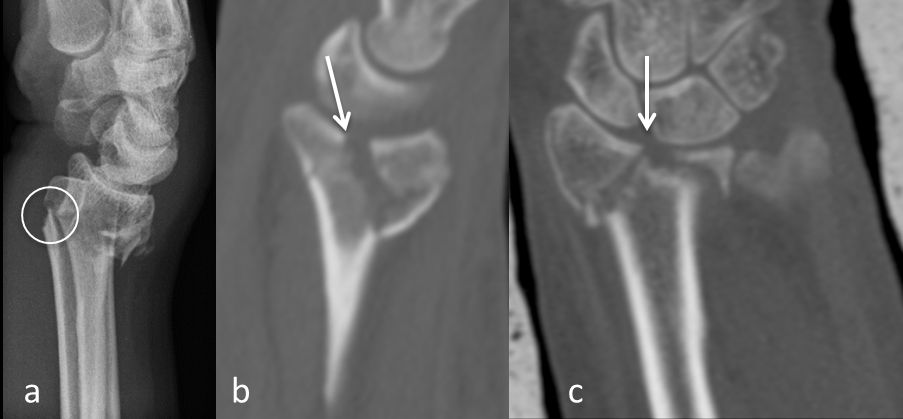

- The displaced palmar cortex (Figure 1a [Fig. 1]).

Figure 1: a: The parameter displaced palmar cortex in a conventional sagittal radiograph (circle). b: The parameter displaced frontal split in a sagittal plane of a CT-scan (arrow). c: The parameter displaced sagittal split in a frontal plane of a CT-scan (arrow). The main parameters of the heuristic.

- The displaced frontal split of the articular surface extending dorsally in the metaphysis (Figure 1b [Fig. 1]).

- The displaced sagittal split of the articular surface (Figure 1c [Fig. 1]).